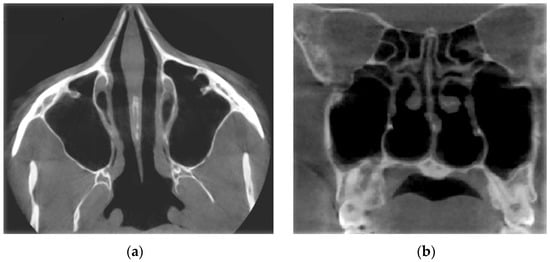

Figure 16 demonstrates the state of the nasal cavity with adenoid vegetations, which can be seen in the images of characteristic sections in axial (Figure 16a) and sagittal (Figure 16b) projections.

From Figure 18, it can be seen that at the conditional norm (curve 1), the coefficient of aerodynamic nasal resistance along the length of the nasal cavity increases sharply in the initial area (in the area of the nasal valve), and then there is a relatively smooth growth. When the nasal septum is curved (curves 2 and 3), there is a sharp increase in the coefficient of aerodynamic nasal drag in areas with cross-section numbers 17–25 (total length about 16 mm) and 25–28 (total length about 6 mm), respectively. The contribution of local aerodynamic drag, which is associated with the curvature of the nasal septum depending on the size of the area, is significantly larger in Figure 12 than with a more local offset. In chronic rhinosinusitis (curve 4) with generalized thickening of the mucous membrane of the nasal cavity, the coefficient of aerodynamic nasal resistance is greater than in other cases. During adenoid vegetations (curve 5) in the area (27–31, length about 8 mm), there is a rather sharp (but much smaller than in graphs 2 and 3) increase in the coefficient of aerodynamic nasal resistance, due to the location of aerodynamic resistance in a relatively wide distal part nasal cavity at the exit to the nasopharynx (see Figure 16). After conchotomy (curve 6), the aerodynamic resistance of the nasal cavity is significantly reduced and monotonically increases without abrupt changes and extremes, which is caused by a wide air channel.

The data of the functional study using posterior active rhinomanometry (see Figure 19) in the forced respiration actually fully correspond to the obtained analytical calculations in Figure 18. It can be concluded that the lowest air flow is at the curvature of the nasal septum (curves 2 and 3 on Figure 19), especially when the curvature of the nasal septum is in the middle section (curve 2 in Figure 13), which causes significant overlap of air flow by local resistance and subsequent turbulence of the flow for a considerable length. With generalized narrowing of the nasal canal due to chronic rhinosinusitis (curve 4 and Figure 14) there is also a fairly low air flow, but this is achieved due to a greater pressure drop, and as a consequence, the largest of these pathological coefficients of aerodynamic nasal drag with high pressure has a loss in length. Adenoid vegetations (curve 5 and Figure 16), also due to local narrowing in the nasopharynx, contribute to increased aerodynamic nasal resistance, but its increase is significantly (approximately twice) less than in the effects of chronic rhinosinusitis and curvature of the nasal septum.